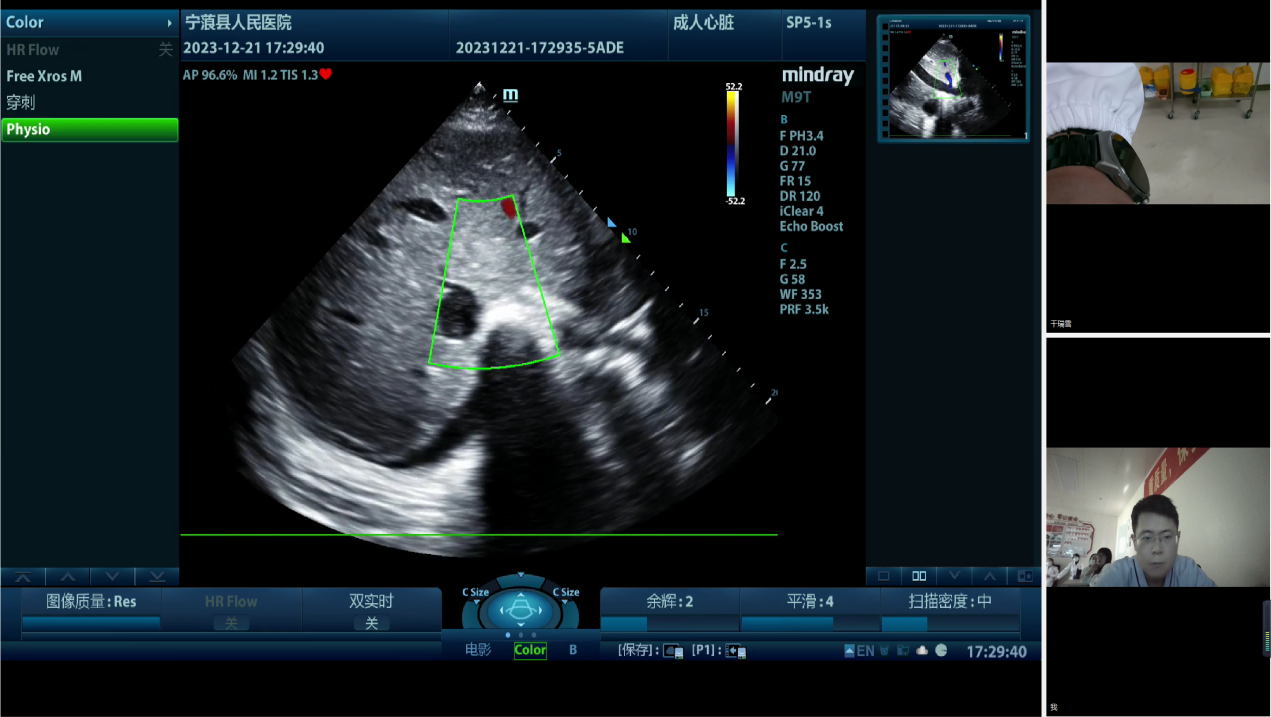

重症医学科主任万林骏等的远程会诊指导下,在宁蒗彝族自治县人民医院重症医学科全体医护、驻宁蒗彝族自治县人民医院对口帮扶附二院重症医学科主治医师张瑞凌的全力配合下,成功抢救了一名在分娩时突发呼吸心跳骤停的22岁年轻孕产妇。借助重症超声远程质控会诊平台,上级医院和基层医院实现上下联动,可持续地促进优质医疗资源下沉,服务于更多的患者。

2023年12月的一个晚上,在宁蒗彝族自治县基层医院的手术室内,一名22岁的年轻妈妈正在经历生死时速。产妇在剖宫产术中,胎儿娩出时,突发呼吸心跳骤停。在医护人员为她进行心肺复苏后,她的生命体征极不稳定,一场急救接力赛立即开始。产妇转入了宁蒗彝族自治县人民医院重症医学科进一步高级生命支持。当晚进行了动脉穿刺置管、静脉穿刺置管、连续性血液净化、强心、肺保护、气道管理等治疗……一整夜过去,产妇依然在鬼门关徘徊。

为进一步讨论治疗方案,宁蒗彝族自治县人民医院重症医学科通过“重症超声远程质控会诊平台”邀请樱花动漫 、丽江市人民医院重症医学科专家及院内专家多学科联合会诊。樱花动漫 重症医学科万林骏教授、万晓红主任医师、朱炜华副主任医师分别针对循环、呼吸、器官保护等提出治疗建议,并与丽江市人民医院重症医学科陈一峰科主任等专家讨论了下一步优化治疗的方案。